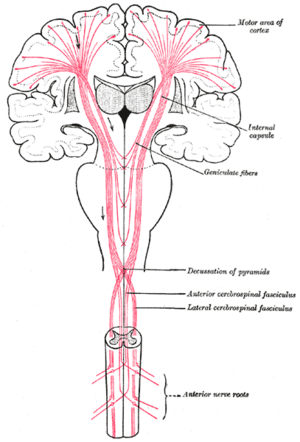

The corticospinal tract constitutes a large part of the internal capsule, carrying motor information from the primary motor cortex to the lower motor neurons in the spinal cord. Above the basal nuclei the corticospinal tract is a part of the corona radiata, below the basal nuclei the tract is called crus cerebri (a part of the cerebral peduncle) and below the pons it is referred to as the corticospinal tract.

The anterior two-thirds of the occipital part of the internal capsule contains fibers of the corticospinal tract, which arise in the motor area of the cerebral cortex and, passing downward through the middle three-fifths of the base of the cerebral peduncle, are continued into the pyramids of the medulla oblongata.

Coronal section of brain immediately in front of pons. Dissection showing the course of the cerebrospinal fibers.

Dissection showing the course of the cerebrospinal fibers. Diagram of the tracts in the internal capsule.